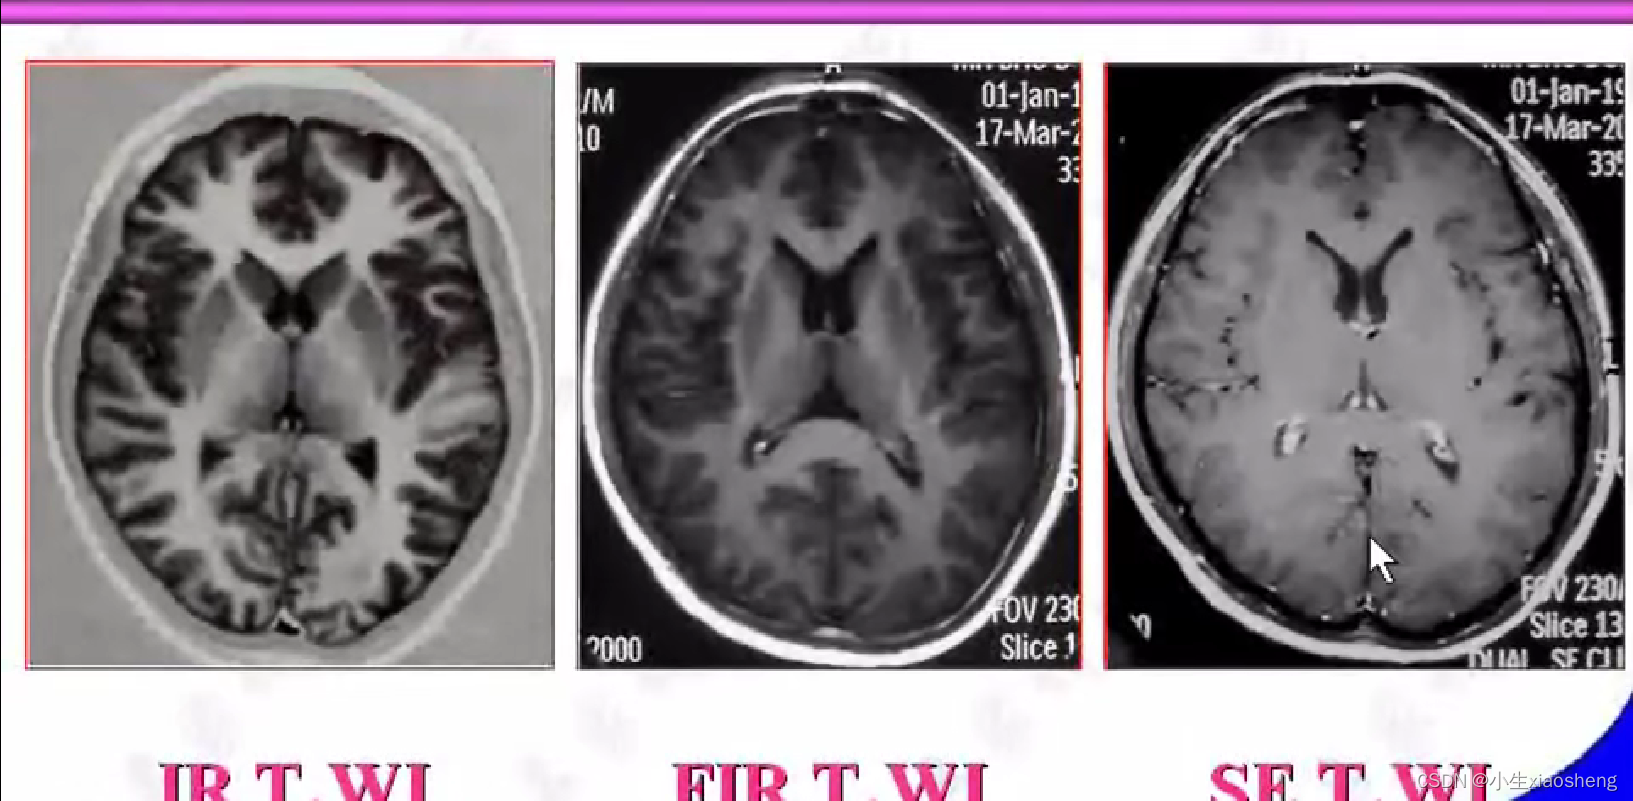

四、反转恢复类序列

1.反转恢复序列

说明时间越长对应的差距也就越大,说明其结果对比好,更容易看出图片。其中TI为反转时间

2.快速反转恢复序列

通过抑制那么在检查的时候就能针对性检查某种组织信号。几种应用我也不想看了😵